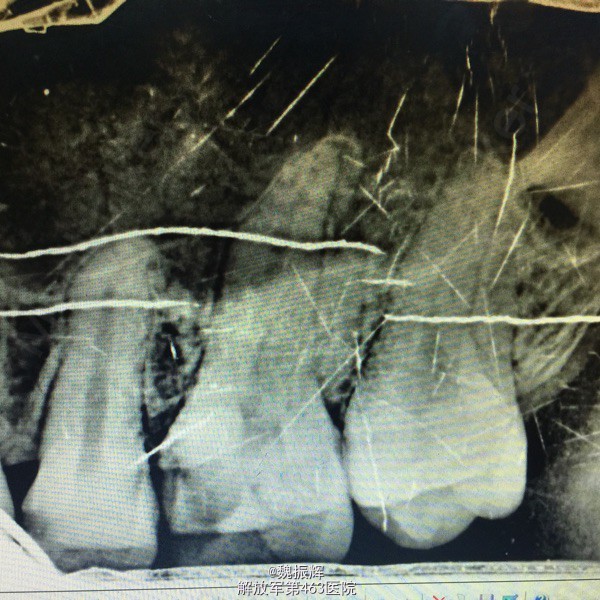

患者男性,23岁,左上后牙食物嵌塞痛数周,近日有自发痛夜间痛表现。影响进食,睡眠。来院就诊。

26的近中龋坏,探(+),冷(+),叩(-),X线示龋坏近髓达髓角。

诊断:26牙髓炎 处理:局麻下,26调合,去腐,开髓,拔髓,疏通根管,根管预备,根管冲洗,行一次性根管充填,氧化锌暂封。观察准备嵌体修复。